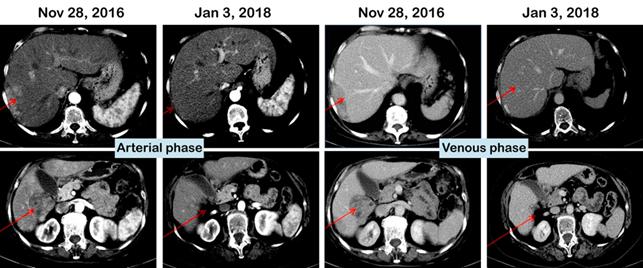

The most impressive finding was that 44% of the patients with Child Pugh B7 treated with Namodenoson were alive at one year compared to 18% in the placebo group. In the overall patient population, among patients who had at least one assessment post baseline, disease control was significant in the Namodenoson group, 26% versus 10% in the control group after four months of treatment, P value 0.013. Among the other positive findings that were presented is the 9% partial response in the Namodenoson treated group vs. 0% in the placebo group. An example of a patient demonstrating an excellent tumor shrinkage was presented. (See Figure 2)

Figure 2